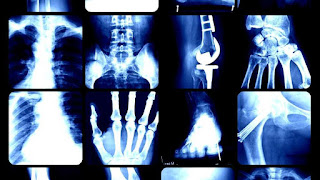

Imaging informatics, also known as radiology informatics or medical imaging informatics, is a subspecialty of biomedical informatics that aims to improve the efficiency, accuracy, usability and reliability of medical imaging services within the healthcare enterprise. It is devoted to the study of how information about and contained within medical images is retrieved, analyzed, enhanced, and exchanged throughout the medical enterprise.

As radiology is an inherently data-intensive and technology-driven specialty of medicine, radiologists have become leaders in Imaging Informatics. However, with the proliferation of digitized images across the practice of medicine to include fields such as cardiology, ophthalmology, dermatology, surgery, gastroenterology, obstetrics, gynecology and pathology, the advances in Imaging Informatics are also being tested and applied in other areas of medicine. Various industry players and vendors involved with medical imaging, along with IT experts and other biomedical informatics professionals, are contributing and getting involved in this expanding field.